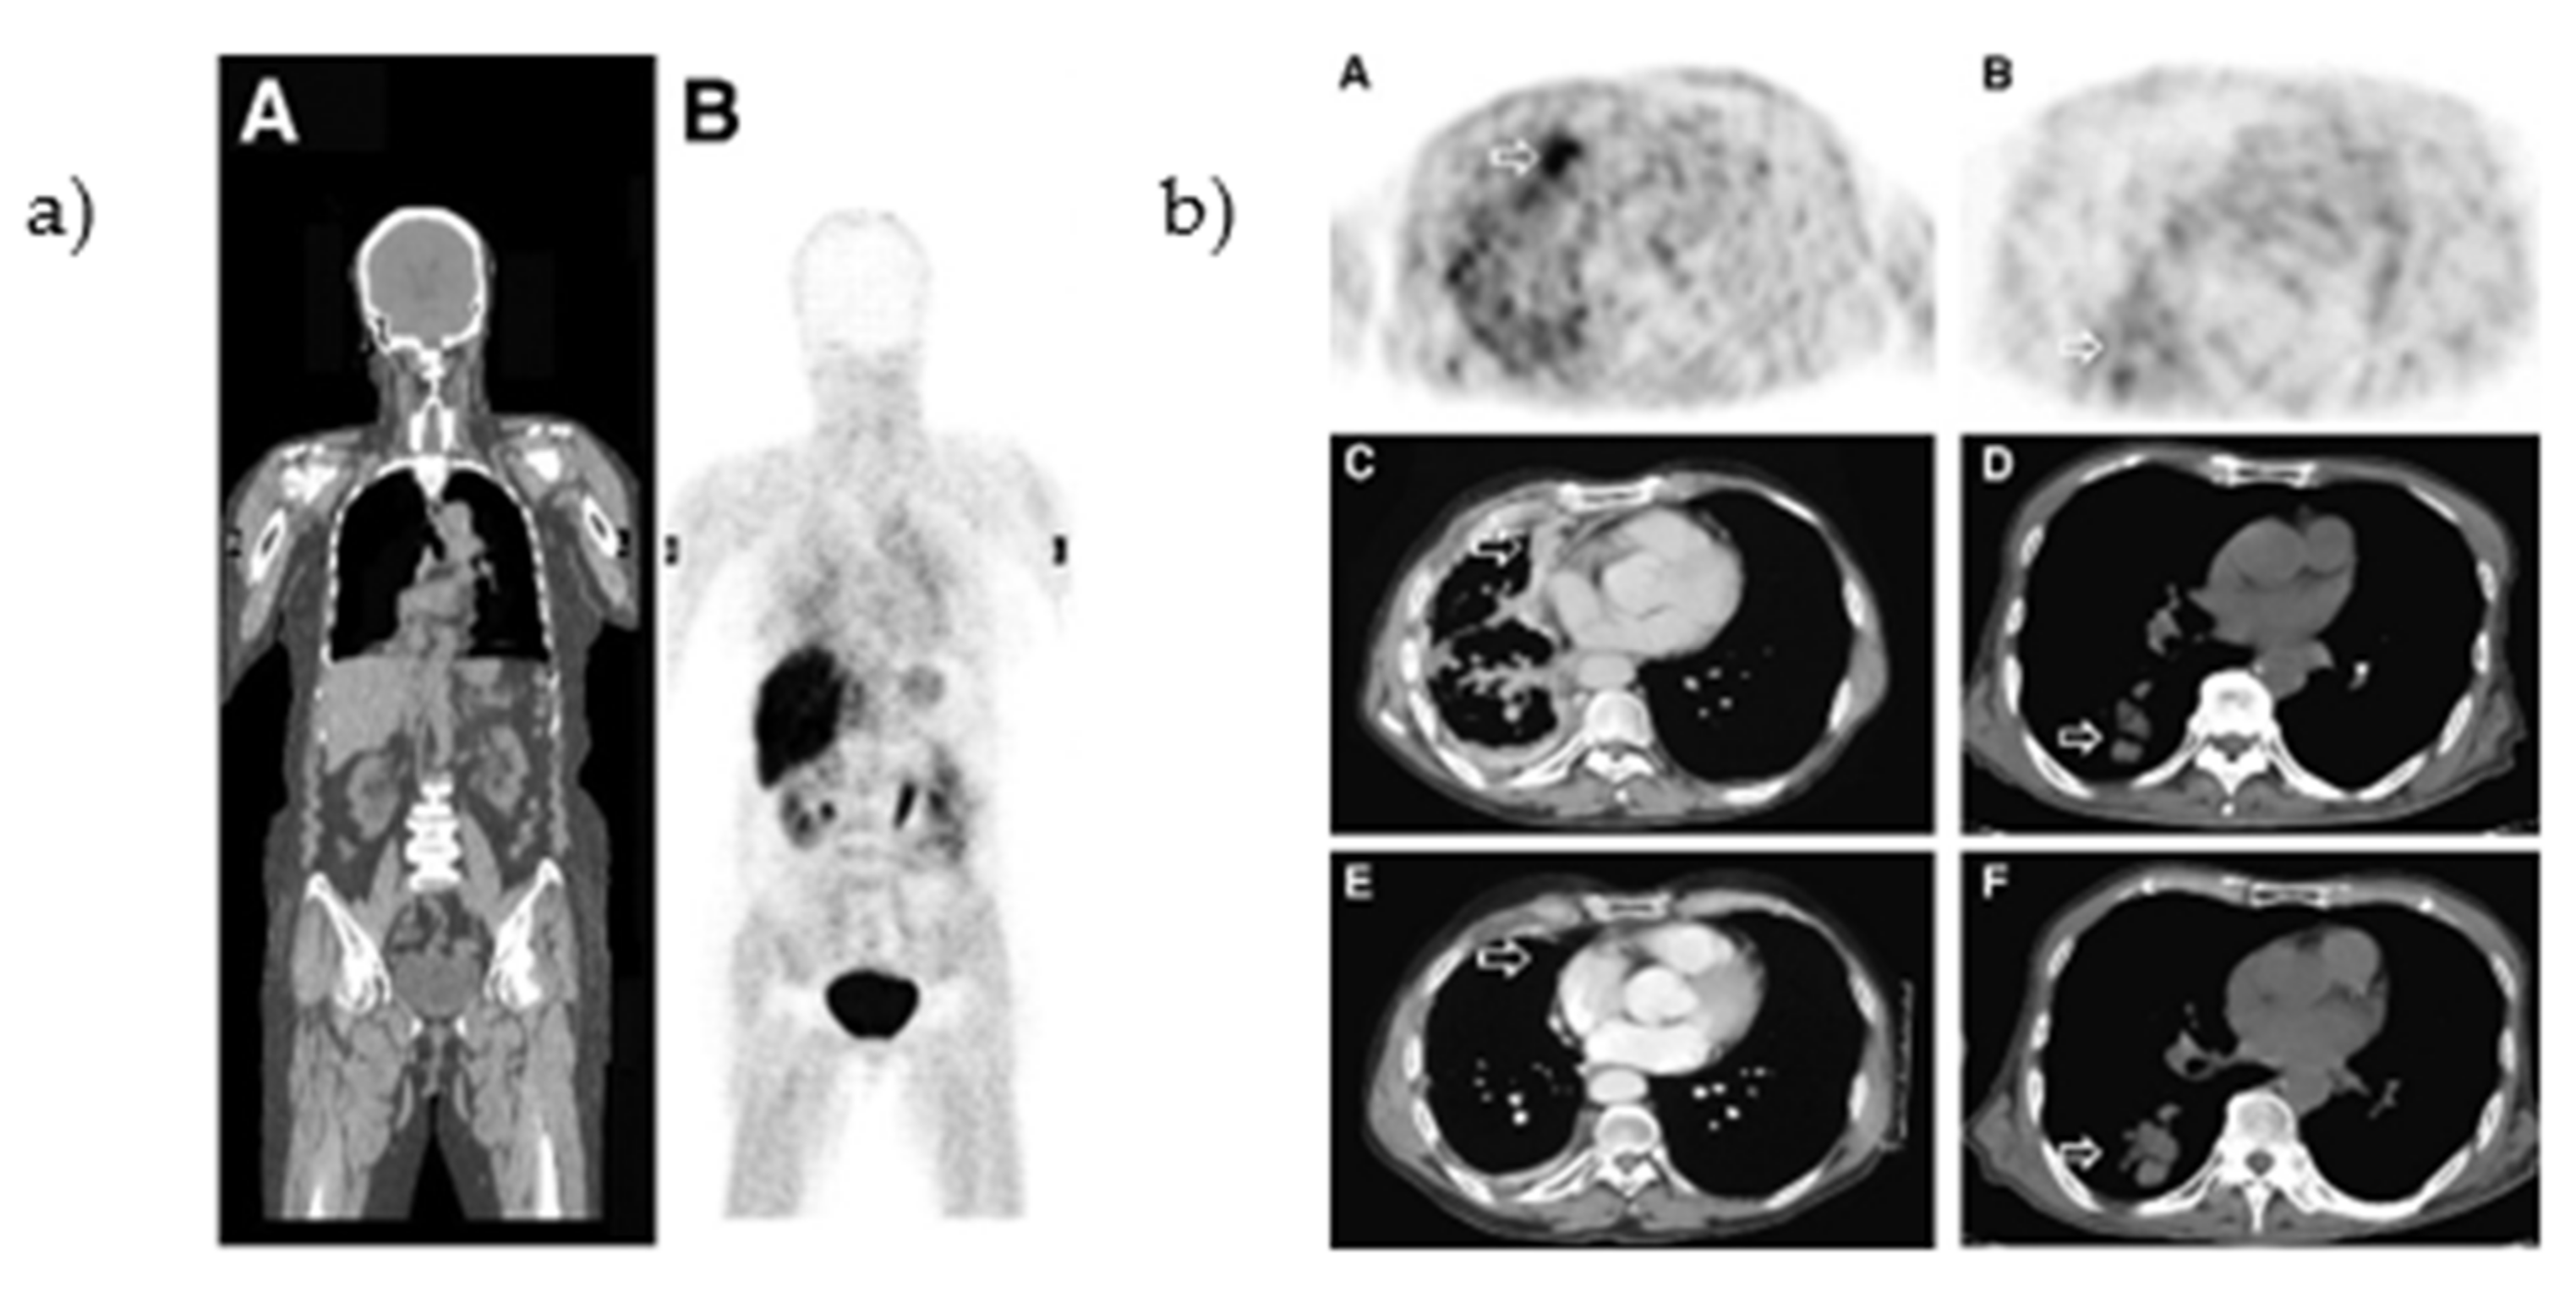

- Memon, A.; Weber, B.; Winterdahl, M.; Jakobsen, S.; Meldgaard, P.; Madsen, H.H.T.; Keiding, S.; Nexo, E.; Sorensen, B.S. PET imaging of patients with non-small cell lung cancer employing an EGF receptor targeting drug as tracer. Br. J. Cancer 2011, 105, 1850–1855. [Google Scholar] [CrossRef]